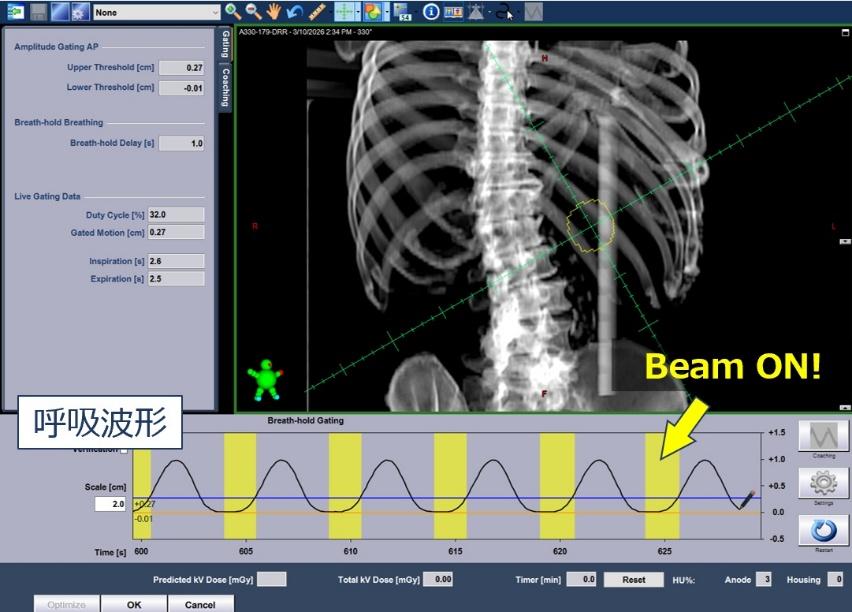

呼吸監視システム(RGSC)

RGSC(Real-time Position Management Respiratory Gating System)は、放射線治療中の患者さんの呼吸による体内の腫瘍や臓器の動きを監視し、より正確なタイミングで放射線を照射するためのシステムです。胸部や腹部の腫瘍は呼吸に伴って位置が動くことがありますが、RGSCでは患者さんの胸部または腹部に設置したマーカーの動きを赤外線カメラで検出し、呼吸状態をリアルタイムで把握します。また、診断CTでは4次元CT(4DCT)を撮影することで、呼吸に伴う腫瘍の動きを動画として確認することができます。

この情報を利用して、呼吸の特定のタイミングに合わせて放射線を照射する呼吸同期照射を行うことができます。腫瘍の動きが小さく安定した呼吸のタイミングで照射することで、より正確な治療が可能になり、周囲の正常組織への影響を抑えることができます。

また、RGSCは呼吸停止照射にも利用されます。これは、患者さんが一定の呼吸状態で息を止めている間に放射線を照射する方法で、特に呼吸によって腫瘍が動きやすい胸部や腹部領域の放射線治療に有効です。システムが呼吸状態を監視しているため、設定した範囲から外れた場合には自動的に照射が停止し、安全に治療を行うことができます。